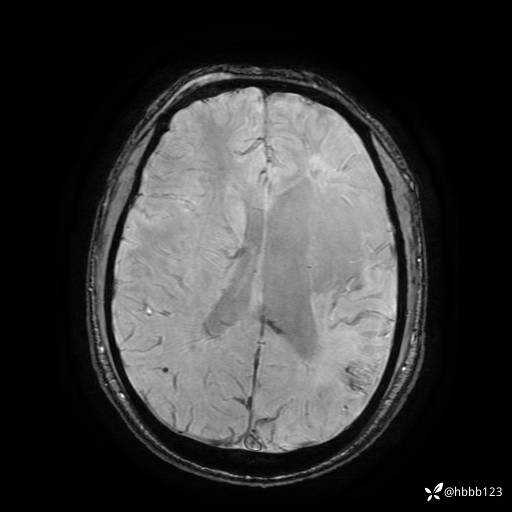

T2 Flair:

T2: